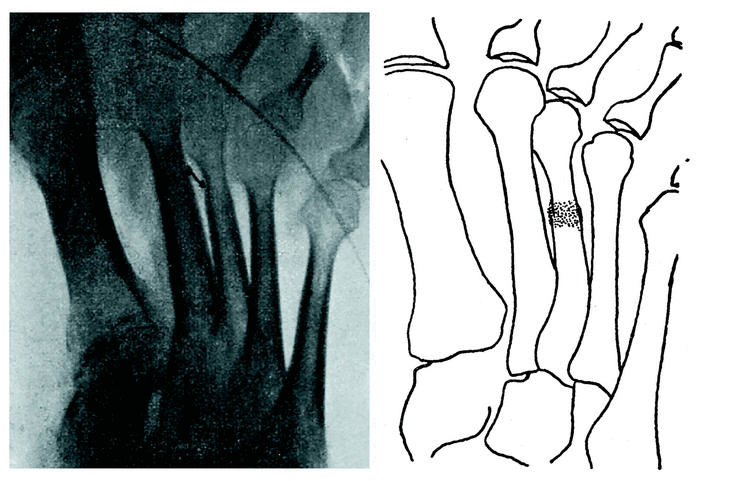

Examen radiográfico

Radiografía anteroposterior (fig. 3): En el tercio superior de la tibia se observa lo siguiente: una fisura de la cortical en su parte interna, reacción perióstica de hueso osteoide en la parte externa, y uniendo ambos, una estrecha zona en la que el hueso parece adensado. Esta zona corresponde al límite entre metáfisis y diáfisis. Radiografía lateral (fig. 3): La cortical de la parte posterior está esfumada en un trayecto de uno y medio centímetros, con reacción perióstica evidente en el mismo punto. En el extremo superior de esta zona, que corresponde al límite entre la esponjosa y metafisaria y la compacta diafisaria, existe una zona transversal más densa que llega hasta el límite anterior del canal medular, sin afectar la cortical anterior.

Figura 3.

Diagnosticamos fractura lenta e incompleta de tibia, ya que un golpe directo hubiera lesionado más bien el borde anterior, que es normal en este caso. Como tratamiento, infiltraciones de novocaína al 1 por 100, sin adrenalina. después de la segunda inyección las molestias subjetivas han desaparecido.

El segundo caso, la simple sintomatología de tumefacción y dolor a la presión nos hace sospechar en una serie de afecciones circunscritas de típica localización en mitad superior de tibia; éstas son: osteomielitis crónica, tuberculosis, goma aislado y sarcoma. Pero el minucioso examen radiológico es el que nos da el diagnóstico. Ante todo, hay que evitar el error de tomar por una línea de fractura la línea epifisaria normal de la tuberosidad anterior de la tibia, que en este caso es bastante irregular (fig. 3). Hablan en pro de la fractura: 1.o, la presencia de la fisura cortical; 2.o, la existencia de la zona transvesal más obscura con la reacción perióstica del hueso osteoide; 3.o, la extensión transversal y no longitudinal del proceso.